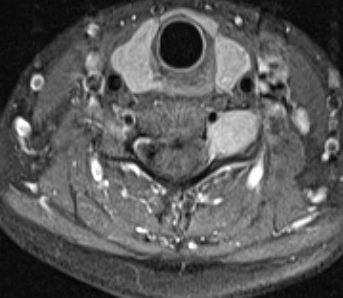

Tumoración en espacio extracanal y extraforaminal, que capta gadolinio de manera homogénea y que se encuentra adherida a arteria vertebral izquierda.

RM axial en T2. Se aprecia schwannoma Tumor tipo IV, según clasificación. Se accedió extracanal, con apertura dural y exéresis intracapsular del tumor con control neurofisiológico.